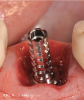

(4.) This series of clinical images illustrates the use of an implant with well-defi ned

threads that improve lateral bone engagement. In a multirooted extraction socket where there are large voids, this can help to achieve initial implant stability.

Figure 4